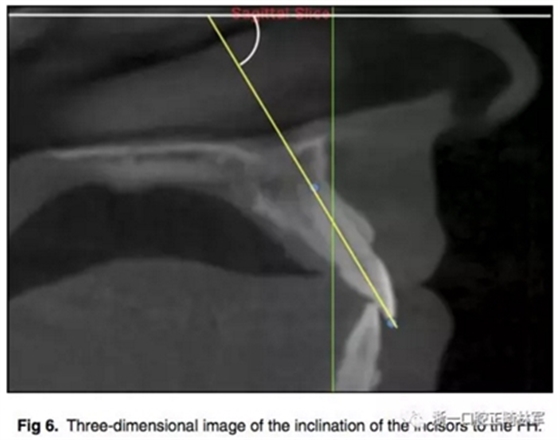

所有圖像導(dǎo)入Dolphin軟件中進(jìn)行處理,2D側(cè)位圖像為使用Dolphin軟件使用相同的標(biāo)準(zhǔn)切割CBCT獲得。使用眶耳平面(FH)作為水平參考平面,使用垂直于眶耳平面(FH)同時(shí)通過(guò)A點(diǎn)的直線作為垂直參考平面。在上切牙最前點(diǎn)進(jìn)行定點(diǎn),牙根分界為自釉牙骨質(zhì)界至根尖,在牙根根尖、牙長(zhǎng)1/2處、釉牙骨質(zhì)界下3mm處進(jìn)行定點(diǎn)。使用FH的平行線測(cè)量頰側(cè)牙槽骨至牙根上3點(diǎn)的距離,同時(shí)測(cè)量A點(diǎn)與以上三條線段的距離,如圖所示。測(cè)量切牙的轉(zhuǎn)矩,使用通過(guò)切點(diǎn)、根尖的直線與FH平面的所成角。

根據(jù)每顆切牙相對(duì)上頜骨的位置在同一平行切面上各自確定A點(diǎn),定好切牙最前點(diǎn)(MFMI),牙根長(zhǎng)度依然為釉牙骨質(zhì)界至根尖點(diǎn)。使用與2D側(cè)位片上相同的方法進(jìn)行牙根至骨皮質(zhì)的測(cè)量。轉(zhuǎn)矩的測(cè)量也同2D側(cè)位片。